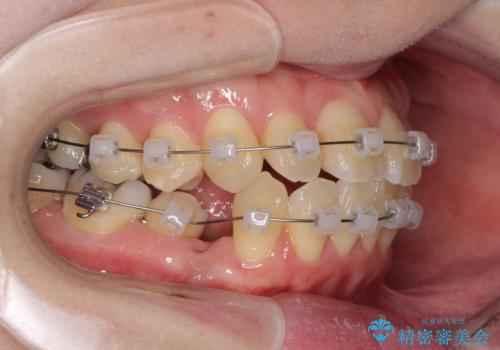

- 矯正装置

- クリアブラケット